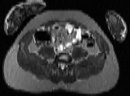

Visible Human male: Sectio transversalis 1769

CT

NMR